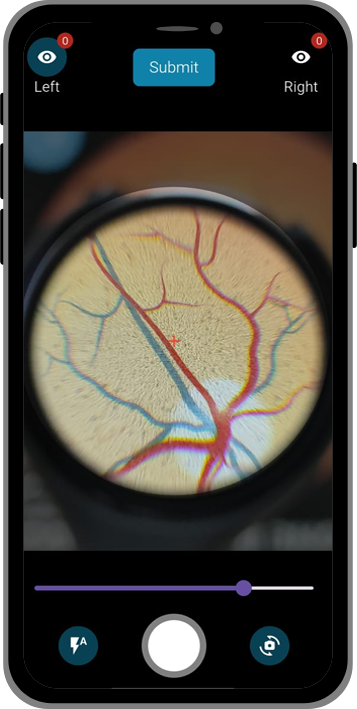

1. Capture

A healthcare worker attaches Lunera to a smartphone and takes retinal images.

2. Analyze

Lunera’s AI model scans the images for signs of DR & other retinal conditions.